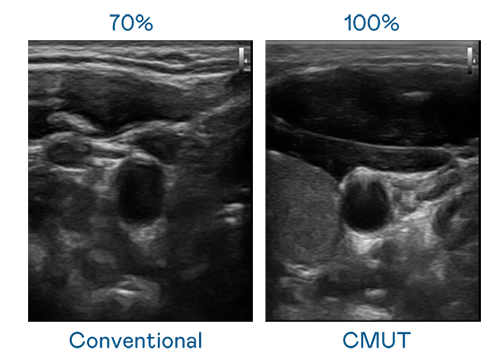

CMUT 技術是一種用電容式微機電元件來產生超音波訊號的技術。與傳統 PZT 壓電式技術相比,CMUT 頻寬增加 30%,更寬頻的超音波訊號讓影像解析度大幅提升,是實現高影像品質醫療超音波掃描、促進精準醫療發展的關鍵技術。

大頻寬帶來超清晰影像

超音波影像的解析度高低,首先取決於探頭能發出的訊號頻寬。CQ9电子 CMUT 可提供高清晰的超音波訊號,提供高頻寬、高靈敏度、影像紋理細節更高的超音波影像,協助醫護人員縮短影像判讀時間及利用精準的醫療影像進行診斷。